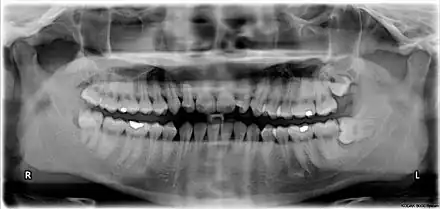

Wisdom teeth in the human mouth for permanent teeth. There are none in deciduous (children's) teeth. | |

The third molar, commonly called wisdom tooth, is the most posterior of the three molars in each quadrant of the human dentition. The age at which wisdom teeth come through (erupt) is variable,[1] but this generally occurs between late teens and early twenties.[2] Most adults have four wisdom teeth, one in each of the four quadrants, but it is possible to have none, fewer, or more, in which case the extras are called supernumerary teeth. Wisdom teeth may become stuck (impacted)[3] and not erupt fully, if there is not enough space for them to come through normally. Impacted wisdom teeth are still sometimes removed for orthodontic treatment, believing that they move the other teeth and cause crowding, though this is no longer held as true.[4][5]

Wisdom teeth (often notated clinically as M3 for third molar) have long been identified as a source of problems and continue to be the most commonly impacted teeth in the human mouth. Impaction of the wisdom teeth results in a risk of periodontal disease and dental cavities.[29] Impacted wisdom teeth lead to pathology in 12% of cases.[30]